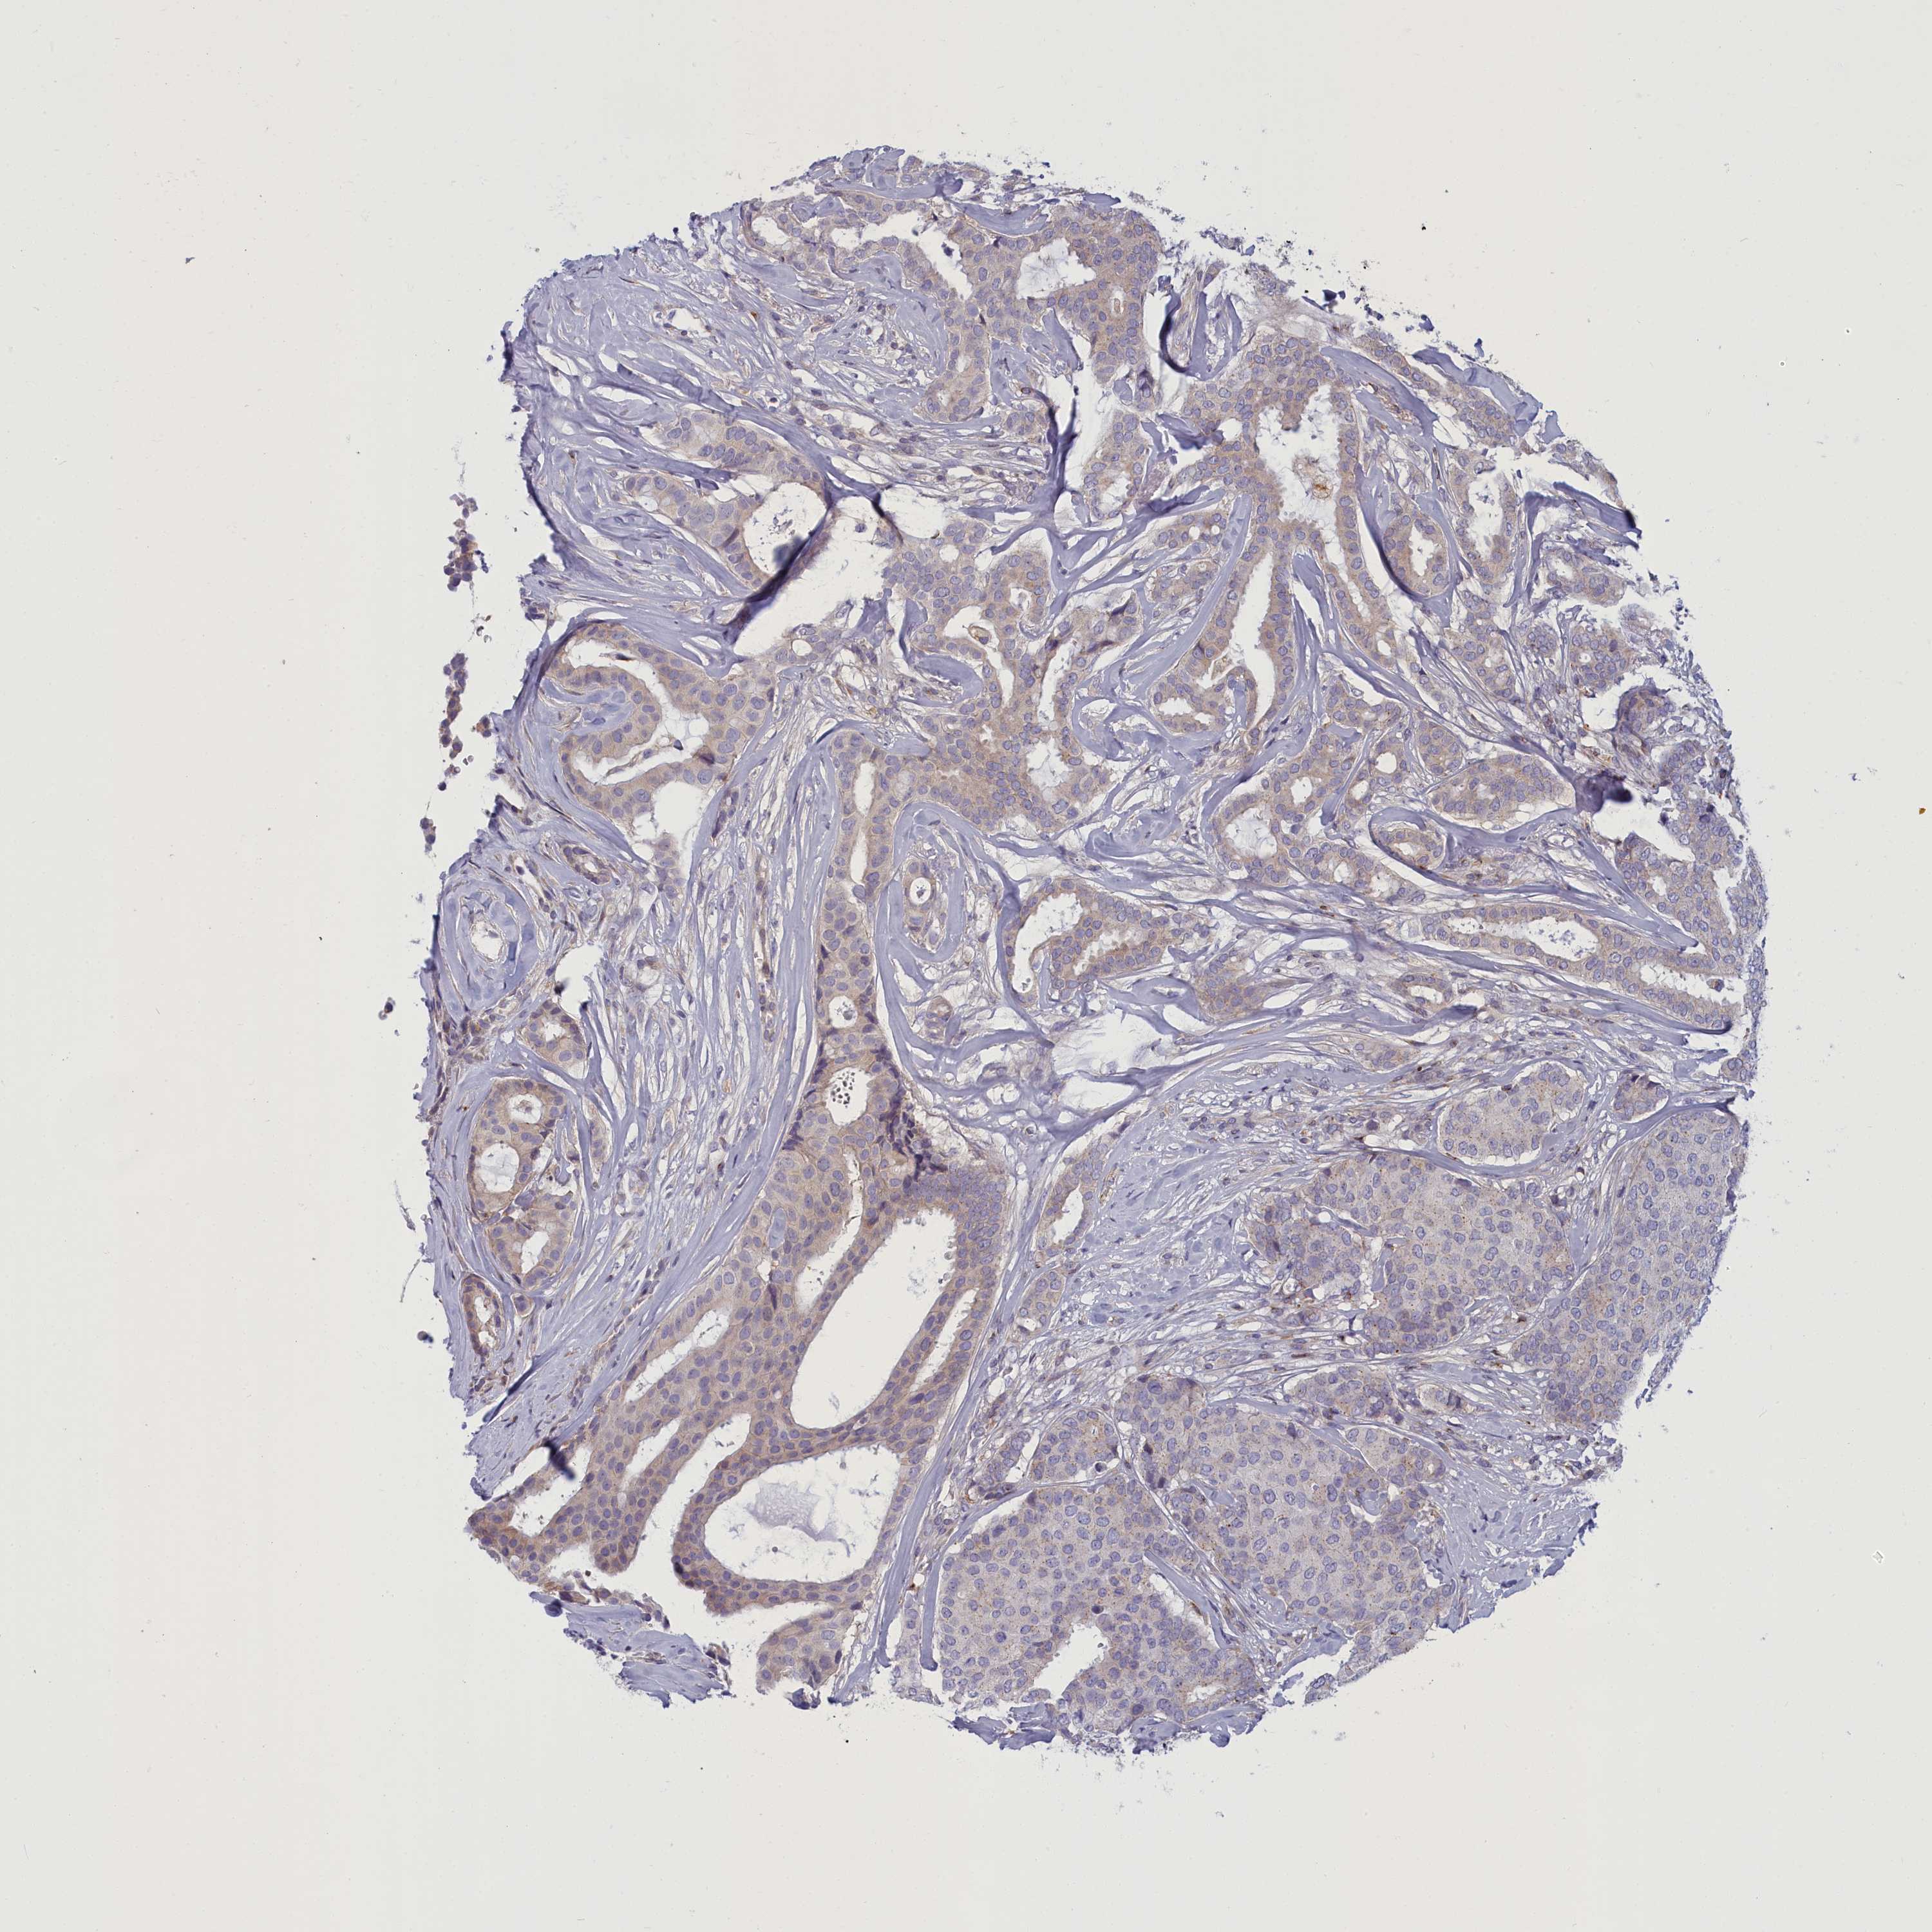

CANCER BREAST CANCER Show tissue menu

BRCA TCGA BRCA VALIDATION PROTEIN EXPRESSION